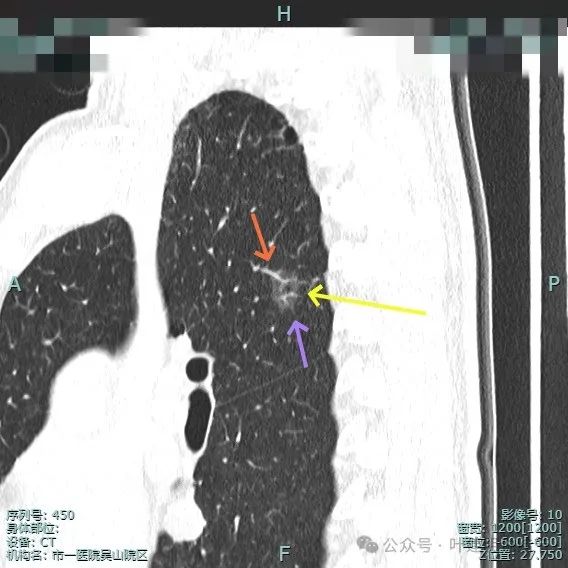

再来看主病灶右上叶后段病灶6的靶重建影像:

病灶磨玻璃密度,未见明显实性成分,但有血管进入。

血管穿行明显,表面有毛刺征,灶内有空泡征。

分叶明显,灶内点状高密度(血管穿行)表面有细小毛刺征。

灶内密度略显不均,有空泡征,表面有毛刺征。

毛刺与血管进入,整体是纯磨,轮廓与边界清。

少许毛刺,整体轮廓清。

血管穿行并发现细小分支的样子,表面不平有细毛刺,灶内有小空泡征。

血管穿行并略有增粗,表面不平有浅分叶,整体轮廓与边界清。

血管进入并有发出分支,边缘有细毛刺,表面不光滑,整体轮廓清,瘤肺边界清楚。